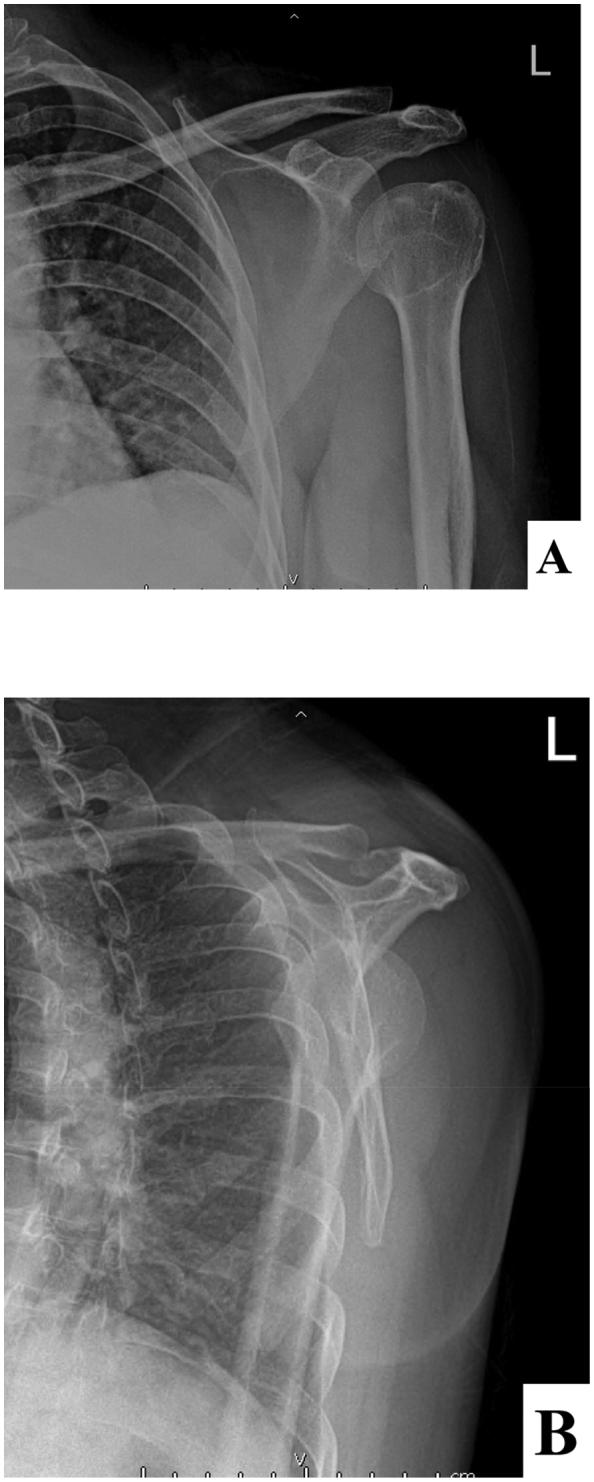

CASE PRESENTATION

A 45-year-old Thai female developed left shoulder septic arthritis after an Astra-Zeneca COVID-19 vaccine administration. The clinical symptoms were left shoulder pain, limited range of motion and fever. The probable risk factors were underlying diabetes mellitus type II and vaccine administration technique. The joint fluid culture showed . This patient was treated with combined arthroscopic debridement and an intravenous antibiotic for 1 week which was then switched to an oral antibiotic for 5 weeks. Her clinical symptoms gradually improved over the 2 weeks following the initiation of treatment.

病例介绍

一名45岁泰国女性在接种阿斯利康新冠疫苗后发生左肩关节化脓性关节炎。临床症状为左肩疼痛、活动范围受限和发热。可能的危险因素为潜在的II型糖尿病和疫苗接种技术。关节液培养显示……该患者接受了关节镜清创术联合静脉注射抗生素治疗1周,之后改为口服抗生素治疗5周。在开始治疗后的2周内,她的临床症状逐渐改善。